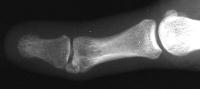

Corrected alignment

Click for larger image

Late result: